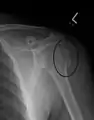

Humerus fracture

Midshaft humerus fracture with callus formation